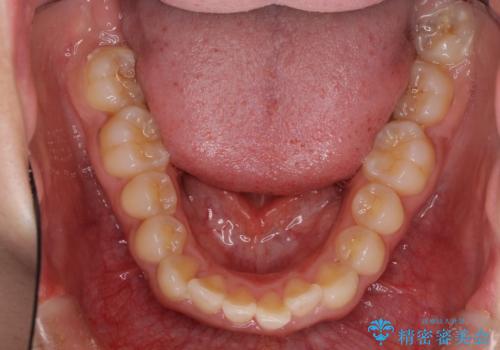

- 口元の突出感と口の閉じにくさを気にして来院された患者様です。

上下左右の小臼歯4本を抜歯し、ワイヤー装置にて口元を引っ込めるよう矯正治療を行うこととしました。

上下顎ともに前突しており、特に上顎は著しい突出感でした。

また、下顎歯列には左右差があり、非対称な抜歯が必要と判断されたため、治療は困難なものとなりました。